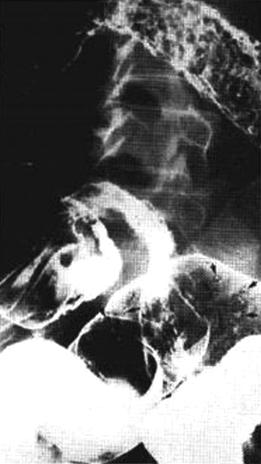

Invertogram d'une

imperforation anus . Image de receuillir a position

inverse on peut en verifie la distance entre

image de distendue gazeuse du cul de sac du colon

avec orifice externe de l'anus ( repair metalique )

. |

Invertogram : Technicque

radiologique sans preparation a position

inverse ( voie image ) avec cliche expose de face et

de profile . Une piece de metal etre place en dehord de anus

. Il y avaite deux forme de malformation : les hautes ( 55%)

s'il la distance du cul de sac du colon terminal a l'anus

depasse de plus > 2 cm , ce type est souvent en associe avec

les autres malformations : urogenitale ( fistule ) ,

rachidienne ( spina malformation ) et cardiaque . Les basses

( 45%) s'il la distance du cul de sac et anus est a moindre

< 2cm et ce forme avait de bon prognostic que la forme

haute